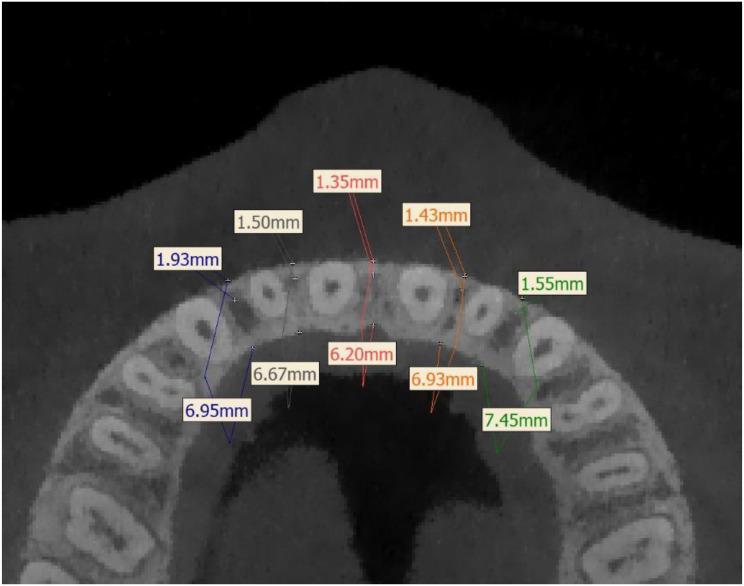

The objective of this retrospective cohort study was to measure the root distance, bone thickness and bone density in maxillary anterior region with different vertical skeletal patterns based on CBCT data, and provide reference for the optimal site for miniscrew insertion in anterior aesthetic region.

60 adult patients(18-29years) with skeletal Class I angle (ANB angle = 2° ± 2°) were selected and divided into three groups (n = 20) according to vertical skeletal patterns.The population was divided into 3 groups according to the measured SN-GoGn angle: hypodivergent (SN-GoGn < 27°), average (27°≤ SN-GoGn ≤ 37°) and hyperdivergent (SN-GoGn > 37°) groups. The CBCT data was processed and measured by Dolphin Imaging and Mimics Medical. Measurement indicators included interradicular distances (IRD), overall bone thickness (OBT), cortical bone thickness (CBT), cortical and cancellous bone density (CoBD & CaBD). One-way ANOVA test of variance was used for statistical comparisons.

IRD increased with apical height, reaching an maximum average measurement of 4.750 ± 1.226 mm at 10 mm axial section. Within the same axial section, the IRD of the region between the two central incisors was significantly larger than that of the other regions. There was no statistical difference in IRD among different vertical skeletal patterns. OBT increased with vertical height in the 2-6 mm axial sections, and no significant difference among three groups. There was a statistical difference of the CBT at 4-8 mm axial sections among the three groups (P < 0.05), but not at 10 mm axial section. There was no statistical difference (P < 0.05) of CaBD among different vertical skeletal patterns. However, there are statistically difference of CoBD in many regions between hypodivergent and hyperdivergent groups.

The anatomical structure in anterior aesthetic region of individuals varies greatly, and interradicular distances is not affected by vertical skeletal pattern. However, in general, hypodivergent patients have higher bone density and greater bone thickness than that of hyperdivergent patients, which means more safe regions to choose for miniscrew insertion.

本回顾性队列研究的目的是基于锥形束计算机断层扫描(CBCT)数据,测量不同垂直骨骼型上颌前部区域的牙根间距、骨厚度和骨密度,为前牙美学区域微螺钉植入的最佳部位提供参考。

选取60例成年患者(18 - 29岁),均为安氏I类骨面型(ANB角 = 2° ± 2°),根据垂直骨骼型分为三组(每组n = 20)。根据测量的SN - GoGn角将人群分为三组:低角型(SN - GoGn < 27°)、平均角型(27°≤ SN - GoGn ≤ 37°)和高角型(SN - GoGn > 37°)。CBCT数据由Dolphin Imaging和Mimics Medical软件处理并测量。测量指标包括牙根间距(IRD)、整体骨厚度(OBT)、皮质骨厚度(CBT)、皮质骨和松质骨密度(CoBD和CaBD)。采用单因素方差分析进行统计学比较。

牙根间距随根尖高度增加,在轴向10mm处达到最大平均测量值4.750 ± 1.226mm。在同一轴向平面内,两颗中切牙之间区域的牙根间距显著大于其他区域。不同垂直骨骼型之间的牙根间距无统计学差异。在轴向2 - 6mm平面内,整体骨厚度随垂直高度增加,三组之间无显著差异。三组在轴向4 - 8mm平面内的皮质骨厚度有统计学差异(P < 0.05),但在轴向10mm平面内无差异。不同垂直骨骼型之间的松质骨密度无统计学差异(P < 0.05)。然而,低角型和高角型组在许多区域的皮质骨密度有统计学差异。

个体前牙美学区域的解剖结构差异很大,牙根间距不受垂直骨骼型影响。然而,一般来说,低角型患者比高角型患者具有更高的骨密度和更大的骨厚度,这意味着微螺钉植入有更多安全区域可供选择。